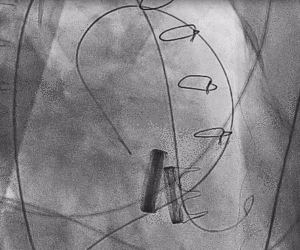

3.经股静脉入路送入16F E-sheath可扩张导管鞘,随后送入SAPIEN 3球扩瓣1输送系统,由于肺动脉入路朝上走,无需调弯,顺利跨瓣,将SAPIEN 3球扩瓣送入预定位置。精准定位后,以160次/分快速起搏,并保证1:1完全夺获,缓慢释放瓣膜。术后超声检查结果显示即刻跨瓣压差从术前9mmHg降至3mmHg,顺利完成瓣膜释放,回撤导管、导丝。

术后随访

术后即刻在杂交手术室拔除气管插管,无气促不适,第二天下床活动,临床症状明显改善。术后一周内康复出院。